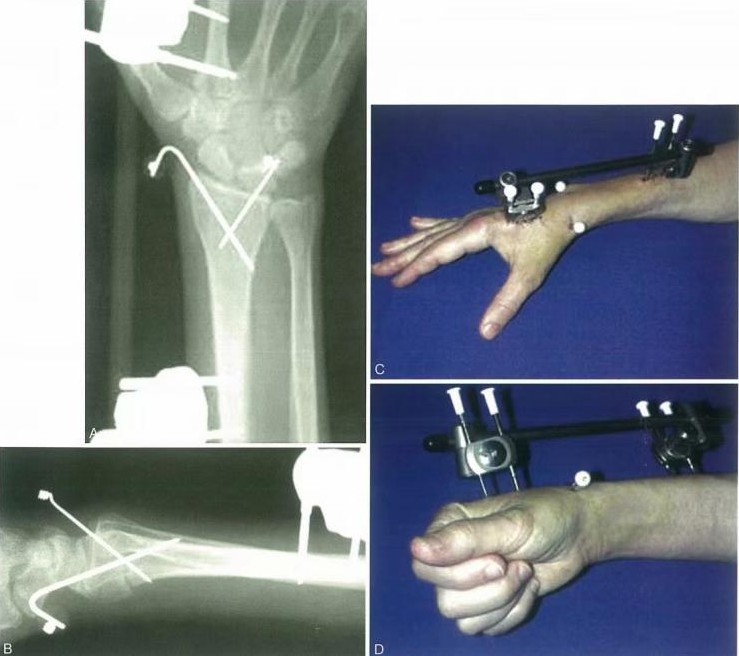

Внешние фиксационные скобки полезны для начальной или дополнительной обработки при определенных переломах дистального радиуса.

Внешний фиксатор нейтрализует осевые напряжения, действующие на дистальный радиус во время сокращения групп мышц предплечья. Фиксация может быть или не быть через запястье, или может быть добавлена дополнительная фиксация.

Параллельная тяга не полностью восстанавливает наклон пальма, но нейтральное положение приемлемо. После операции запястье закрепляется в трубчатом литье в вращающемся заднем положении в течение 10 дней, пока боль и отек не исчезнут.